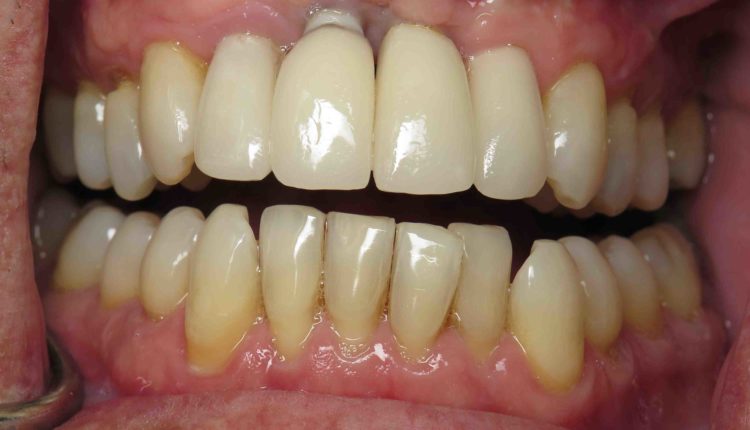

Implants can wear out eventually or without good oral hygiene. Dental implants are not suitable for everyone, few patients may not be eligible for tooth replacement due to their bone health. Dental implants generally require healthy, dense bones. Strong bones in place are a parameter to support dental implants.

When maintained with proper hygiene and controls, dental implants can last a lifetime. The crown attached to the implant will typically need to be replaced every 15 to 20 years, although it can last for decades in some cases.